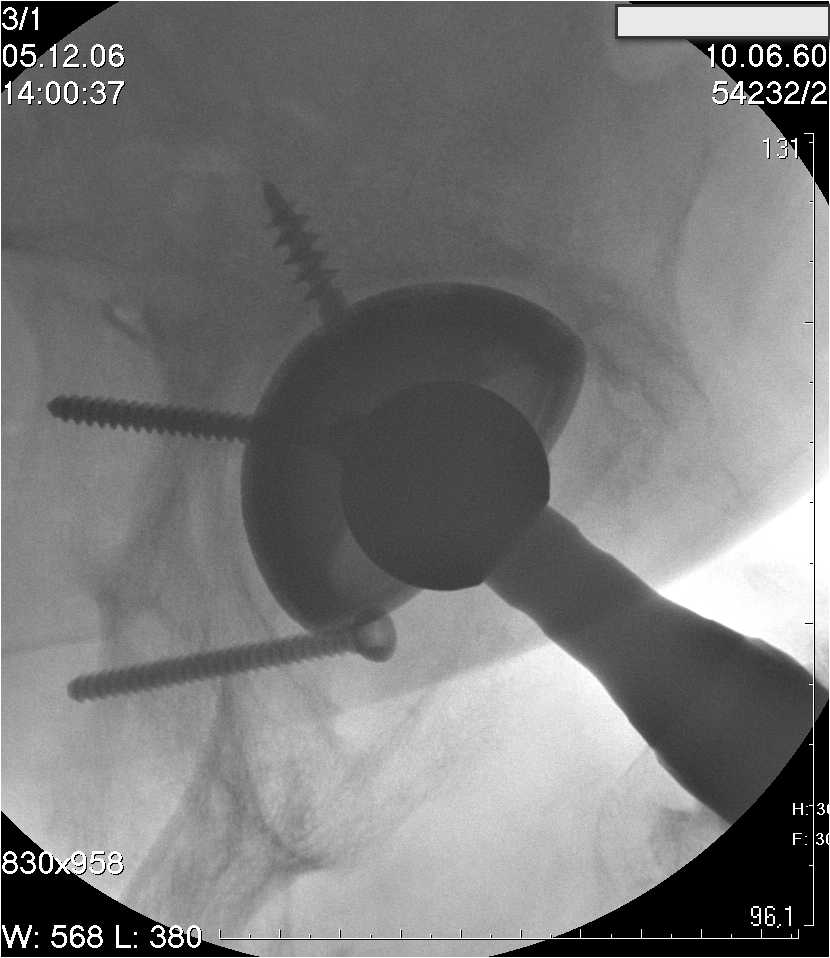

Уважаемые коллеги.В 3 Центральный Военный Клинический Госпиталь имени А. А. Вишневского, что в Красногорске, Московской области, в отделение эндопротезирования крупных суставов поступил пациент 1960 года рождения Жалобы при поступлении: на боли в области левого тазобедренного сустава (больной указывает на точку расположенная в середине условной линии между седалищным бугром и большим вертелом), усиливающиеся в начале ходьбы, при опоре на левую ногу с иррадиацией болей по наружной и наружно-задней поверхности левого бедра, левый коленный сустав; снижение объема движения в левом тазобедренном суставе, снижение опорной способности левой нижней конечности, хромоту на левую ногу, необходимость использования дополнительной опоры (костыли) при ходьбе, снижение объема двигательной активности из за болей в суставе.В анамнезе: Со слов больного, согласно медицинских документов, в 1989 году получил травму левой нижней конечности: закрытый перелом левой вертлужной впадины с центральным вывихом головки левой бедренной кости. Лечился консервативное. В процессе лечения сформировался посттравматический артроз, укорочение левой нижней конечности до 5 см. 25.04.2005 года в Подольском Окружном Госпитале Министерства Обороны выполнено: одномоменто, остеосинтез заднего края вертлужной впадины фрагментом резецированной головки бедренной кости и тотальное эндопротезирование левого тазобедренного сустава бесцементным эндопротезом "VERSIS ET" с бесцементной чашкой TRILOGY. Послеоперационный период осложнился ранним нагноением области эндопротеза, в результате санаций очага инфекции и антибиотикотерапии, активного промывного дренирования антисептиками, послеоперационная рана зажила. После операции, со слов больного, через два месяца в полном объеме стал нагружать левую нижнюю конечность. В течение полгода, после операции чувствовал себя вполне удовлетворительно. С марта 2006года стал отмечать появление болей в области тазобедренного сустава, то в области паха, то в области левой ягодицы. С августа месяца отмечает те жалобы, с которыми он сейчас к нам обратился. Температура тела, после заживления раны, нормальная. В анализах крови, лейкоциты около 7 тыс, формула нормальная, СОЭ 12 мм ч. Локально: при осмотре обеих нижних конечностей, анатомическая ось конечности не нарушена; отмечено относительное укорочение левой н\конечности на 1.5 см., гипотрофия мышц левого бедра 3 см, голени 2 см, симптом. Объем движений в тазобедренных суставах: правый~ сгибание- 60 гр, разгибание-180 гр ,отведение- 35 гр, левый~ сгибание- 110 гр , разгибание-170 гр , отведение-15 гр. Контуры других суставов н/конечностей обычные, объем движений в них не страдает. Пульсация на артериях конечностей удовлетворительная. Неврологические нарушения конечностей отсутствуют, рефлексы на обеих н/конечностях одинаковые, чувствительных нарушений нет. Осевая нагрузка на левую нижнюю конечность вызывает боль в точке расположенная в середине условной линии между седалищным бугром и большим вертелом. Отмечается пигментация и пастозность нижней трети обеих голеней и стоп, характерная для посттромботической болезни. На Цветном дуплексном сканировании сосудов нижних конечностей: Нестенозирующий атеросклероз обеих бедренных и подколенных артерий . Гемодинамически значимых препятствий кровотоку в магистральных артериях ног не выявлено. Глубокие и поверхностные вены нижних конечностей проходимы. Умеренная недостаточность клапанов подколенных вен. Данных за тромбоз глубоких вен на момент осмотра не получено.А вот что пишет наш рентгенолог: На серии рентгенограмм области левого тазобедренного сустава определяется тотальный бесцементный эндопротез. Вокруг тени чашки эндопротеза определяется ободок остеорезорбции. Кроме того, визуализируется деформированный костный винт фиксирующий консолидированный отломок вертлужной впадины, вплотную прилегающий к тени чашки эндопротеза. Заключение: Рентгеновские признаки нестабильности чашки тотального эндопротеза. Лучевая нагрузка: 6 мЗв. У нас в отделении разошлись мнения: начальник мой утверждает, после сравнения снимков, принесенных больным от августа и октября 2006года и наших рентгенснимков, что у больного нет нестабильности вертлужного компонента, и что надо назначит курс консервативной терапии: препараты кальция, миакальцик, увеличить осевую нагрузку на левую нижнюю конечность, ЛФК направления на укрепление мышц бедра, ягодиц, физиолечение. А я утверждаю, что у больного клиника нестабильности вертлужного компонента, и необходима ревизия вертлужного компонента, не исключено даже наличие инфекции под чашкой эндопротеза (не смотря на отсутствие клинических признаков инфекции). В результате проводимой консервативной терапии, боли у больного усилились. Помогите рассудить нас, мы готовы выслушать ваши мнения по этому поводу. С уважением Батал Шушания.3 ЦВКГ имени А. А. Вишневского

Ув. Коллега.Четких рентгенологических признаков нестабильности вертлужного компонента действительно нет. Здесь, кроме нестабильности, можно искать причину в поясничный отдел позвоночника(Hip-spain синдром - всё-таки 15 лет ходил с укорочением),либо сделать спиральный КТ и посмотреть, нет ли несращения в области старого перлома вертлужной впадины. Зачастую ложные суставы подвздошной, седалищной, а иногда и лонной костей являются причинами несостоятельности эндопротезов.

Уважаемый д-р Батал,

Ситуация не столь однозначная как Вам это видится. По подробно описываемой клинике с большей вероятностью речь идет о проблемах

поясничного отдела позвоночника. Есть зона остеолиза вокруг чашки, но как правило, дополнительный винт держит чашку достаточно хорошо, и даже при наличии микроподвижности, это не сопровождается столь ярким болевым синдромом. Поэтому, я бы сделал следующее: МРТ позвоночника, пункцию ТБС для исключения инфекционного процесса. Ревизию рассматривал бы как крайний вариант, учитывая выполненную костную пластику и отсутствие явных признаков нестабильности.

уважаемый коллега, Антон Вакуленко. Спасибо за четкий, расписанный по пунктам план действий. При поступлении пациента в отделение, я думал точно как вы. Но на следующий день, выполнил многопроеционное рентгенисследование, показал невропатологу, и доложил начальнику отделения о больном.После разбора пришли к следующему, да у больного действительно нестабильность вертлужного компонента, есть зона лизиса в месте костного аутотрансплантата, а в месте фиксаци чашки деротационным винтом четко выраженный контакт чашки с костной тканю. Мы пришли к выводу,что лизис костного аутотрансплантата из за осевой перегрузки на фоне незавершенного ремоделирования (вес больного 130 кг). Потому мы и приняли план вышеуказанного лечения. Провели беседу с больным, больной согласился с нами. Через 3-6 месяцев мы оценим эффективность лечения и доложу. Возможно и придется тогда идти на ревизию с заменой только вертлужного компонента а может и придется удалить весь эндопротез с установкой спейсера.. посмотрим.....